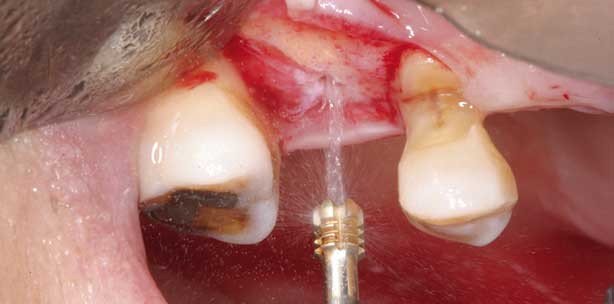

Ein 49-jähriger Mann mit fehlendem Zahn 16 stellte sich in unserer Abteilung mit dem Wunsch nach einer implantatgestützten prothetischen Restauration vor. Zahn 16 war vier Wochen zuvor extrahiert worden. Die Anamnese des Patienten war unauffällig. Ein präoperatives Computertomogramm zeigte in Regio 16 eine Restknochenhöhe von 5 mm (Abb. 1). Der Eingriff erfolgte unter Lokalanästhesie. Zunächst wurde ein Mukoperiostlappen gebildet, um den Alveolarknochen freizulegen. Der Sinusboden wurde mit einem piezoelektrischen Ultraschallgerät, das mit einem runden Hartmetalleinsatz kombiniert war, eröffnet. Zu diesem Zeitpunkt ließ sich die genaue Knochenhöhe vom Kieferkamm bis zum Kieferhöhlenboden bestimmen. Die Sinusmembran war nach der Durchtrennung des Sinusbodens erkennbar (Abb. 2). Ein HPISE-Einsatz wurde vorgeschoben, um die Sinusmembran mit Wasserdruck anzuheben; gleichzeitig wurde der Osteotomiespalt aufgeweitet (Abb. 3). Mit einem Tri-Spade-Bohrer erfolgten intermittierende Bohrungen, um Platz für das 11 mm lange ANKYLOS®-Implantat (DENTSPLY Implants, Mannheim) mit 5,5 mm Durchmesser zu schaffen (Abb. 4). In den unter der angehobenen Sinusmembran entstandenen neuen Raum wurde autologes Fibringel mit konzentrierten Wachstumsfaktoren eingebracht, um die Knochenneubildung in der Kieferhöhle zu beschleunigen (Abb. 5). Das Implantat wurde mit guter Primärstabilität inseriert und ein Gingivaformer eingeschraubt (Abb. 6). In die Extraktionsalveole wurde ein mineralisiertes Allotransplantat eingebracht und mit dem Lappen abgedeckt (Abb. 7). Das Querschnittsbild des postoperativen Computertomogramms zeigte in Regio 16 eine allein durch den hydraulischen Druck erzielte vertikale Anhebung der Kieferhöhlenschleimhaut von etwa 6 mm (Abb. 8). Im Gegensatz zu klassischen Sinusbodenelevationen mit Osteotomen wurde die Sinusmembran sowohl an der medialen wie auch an der lateralen Wand gleichmäßig durch den hydraulischen Druck angehoben, wie dies auch bei herkömmlichen Augmentationen mit lateralem Zugang zu sehen ist. Nach fünf Monaten Einheilzeit wurde die Abformung vorgenommen. Zwei Wochen nach der Abformung wurde eine Metallkeramikkrone eingesetzt und zementiert (Abb. 9 und 10).

Ein 66-jähriger Mann wurde in unserer Abteilung mit dem Wunsch nach einer Restauration der fehlenden Zähne 16, 14, 24 und 36 vorgestellt. Eine präoperative Kegelstrahlcomputertomografie (CBCT) zeigte an der Position des fehlenden Zahns 16 eine Knochenhöhe von etwa 5 mm (Abb. 11). Der Sinusboden wurde mit einem runden Hartmetalleinsatz gefenstert; zu diesem Zeitpunkt wurde eine Knochenhöhe von 5mm gemessen (Abb. 12 und 13). Der HPISE-Einsatz kam zur Anwendung, um die Sinusmembran mit hydraulischem Druck vorsichtig anzuheben und gleichzeitig die Präparation aufzuweiten. Der HPISE-Einsatz wurde in den neu geschaffenen Raum unter der angehobenen Membran vorgeschoben (Abb. 14 und 15). Das Implantatbett wurde wie im ersten Fall mit einem Tri-Spade-Bohrer erweitert. Bei jedem Atemzug war die Auf- und Abwärtsbewegung der Sinusmembran zu beobachten (Abb. 16). Um die Knochenneubildung in der Kieferhöhle zu beschleunigen, wurde in den neu geschaffenen Raum unter der angehobenen Sinusmembran autologes fibrinreiches Gel eingebracht (Abb. 17). Anschließend wurde ein 11 mm langes ANKYLOS®-Implantat mit 4,5 mm Durchmesser mit guter Primärstabilität inseriert (Abb. 18). An der Position der fehlenden Zähne 14 und 24 wurde eine ultraschallgestützte piezoelektrische Kieferkammspreizung durchgeführt und ein 11 mm langes ANKYLOS®-Implantat mit 3,5 mm Durchmesser inseriert. Der Kamm wurde mit autogenem Knochenmehl augmentiert und mit einer Fibringelbarriere abgedeckt (Abb. 19–21). Das postoperative Röntgenbild zeigt eine Membrananhebung über den Implantatapex (Abb. 22). An der Position des fehlenden Zahns 36 wurde ein 9,5 mm langes Implantat mit 4,5 mm Durchmesser platziert. Zur horizontalen und vertikalen Augmentation wurde eine Mischung aus bovinem Knochen und mit Gel konditioniertem Allotransplantat eingesetzt. Das Knochentransplantat wurde mit einem Titangitter abgedeckt und mit einem Gingivaformer stabilisiert (Abb. 23).